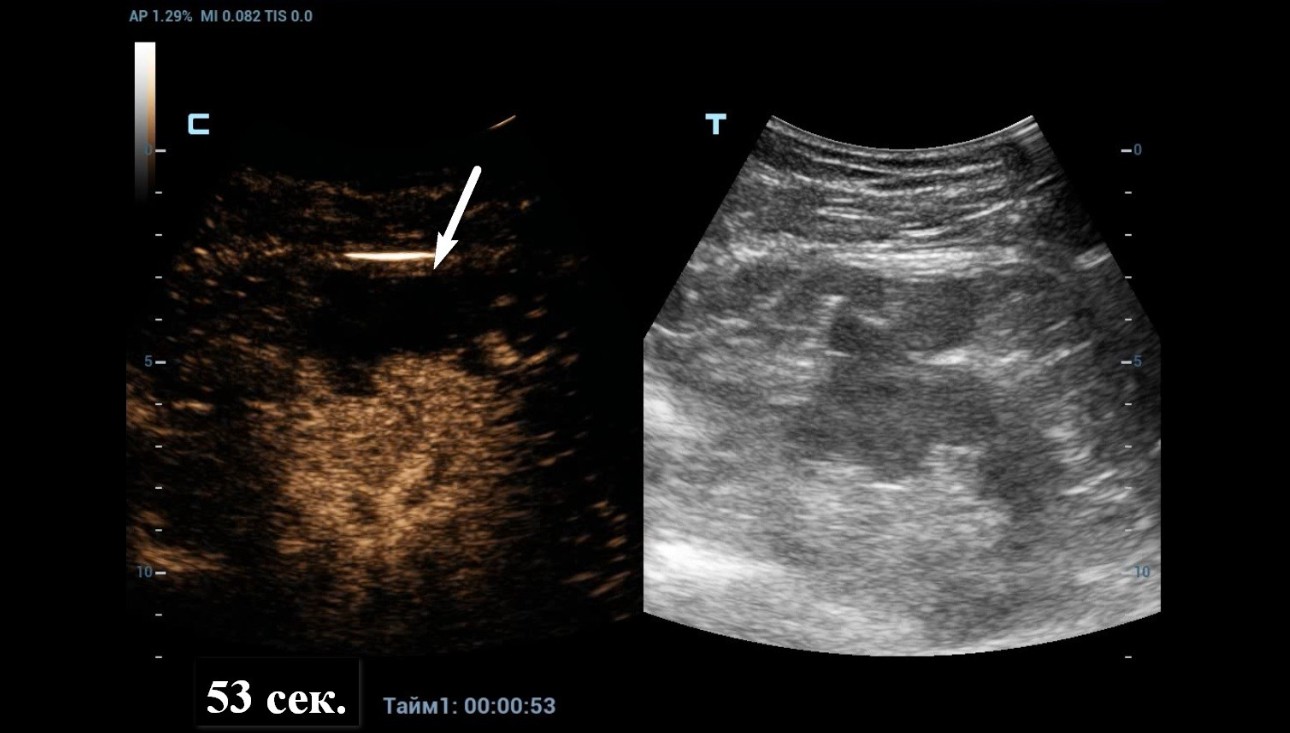

As Power Doppler showed indeterminate results regarding internal flow within the complex cystic mass, CEUS was performed through injection 1.2 ml of Sonovue (Bracco Swiss, SA, Switzerland). The longitudinal plane of the kidney with the maximum section of the cystic mass was selected for scanning. At the end, the cystic mass was characterized as benign by a lack of enhancement throughout the CEUS study (Figure 4 and 5).

Quantitative analysis also confirmed the absence of enhancement within the cystic mass (Figure 6).